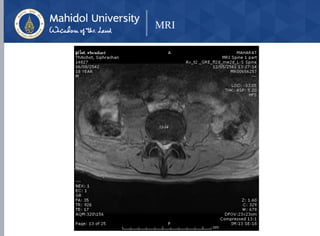

MRI

Herniated Nucleus Pulposus at L3-L4, L4-L5

With cauda equina syndrome

• MRI

• Modality of choice

• Indications for obtaining an MRI

• pain lasting > 1 month and not responding to

nonoperative management

• Red flags are presentenerative changes